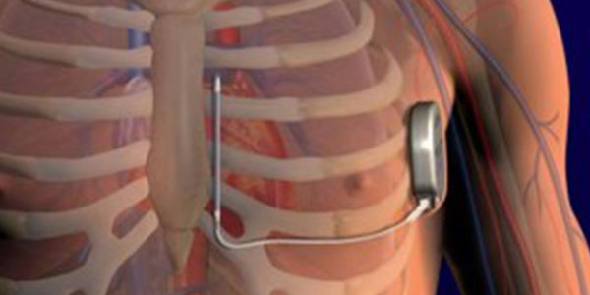

The S-ICD provides effective defibrillation for ventricular

tachyarrhythmias , significantly reduces the risk of vascular

injury at the time of implant, has a low risk of systemic infection

given no hardware in the venous system, preserves venous access

(a high priority for some patients including those with end-stage

renal disease who are on or are preparing for hemodialysis), avoids

risks associated with endovascular lead extraction if future lead

fracture or infection, and again requires no fluoroscopy at the time of implant.

Your electrophysiologist will able to discuss this option more in-depth with you

to determine if you are a good candidate and proceed with in-office required preoperative 3-lead

surface electrocardiogram screening to ensure that you are a reasonable candidate

for this therapy (given the appropriateness of surface signals).